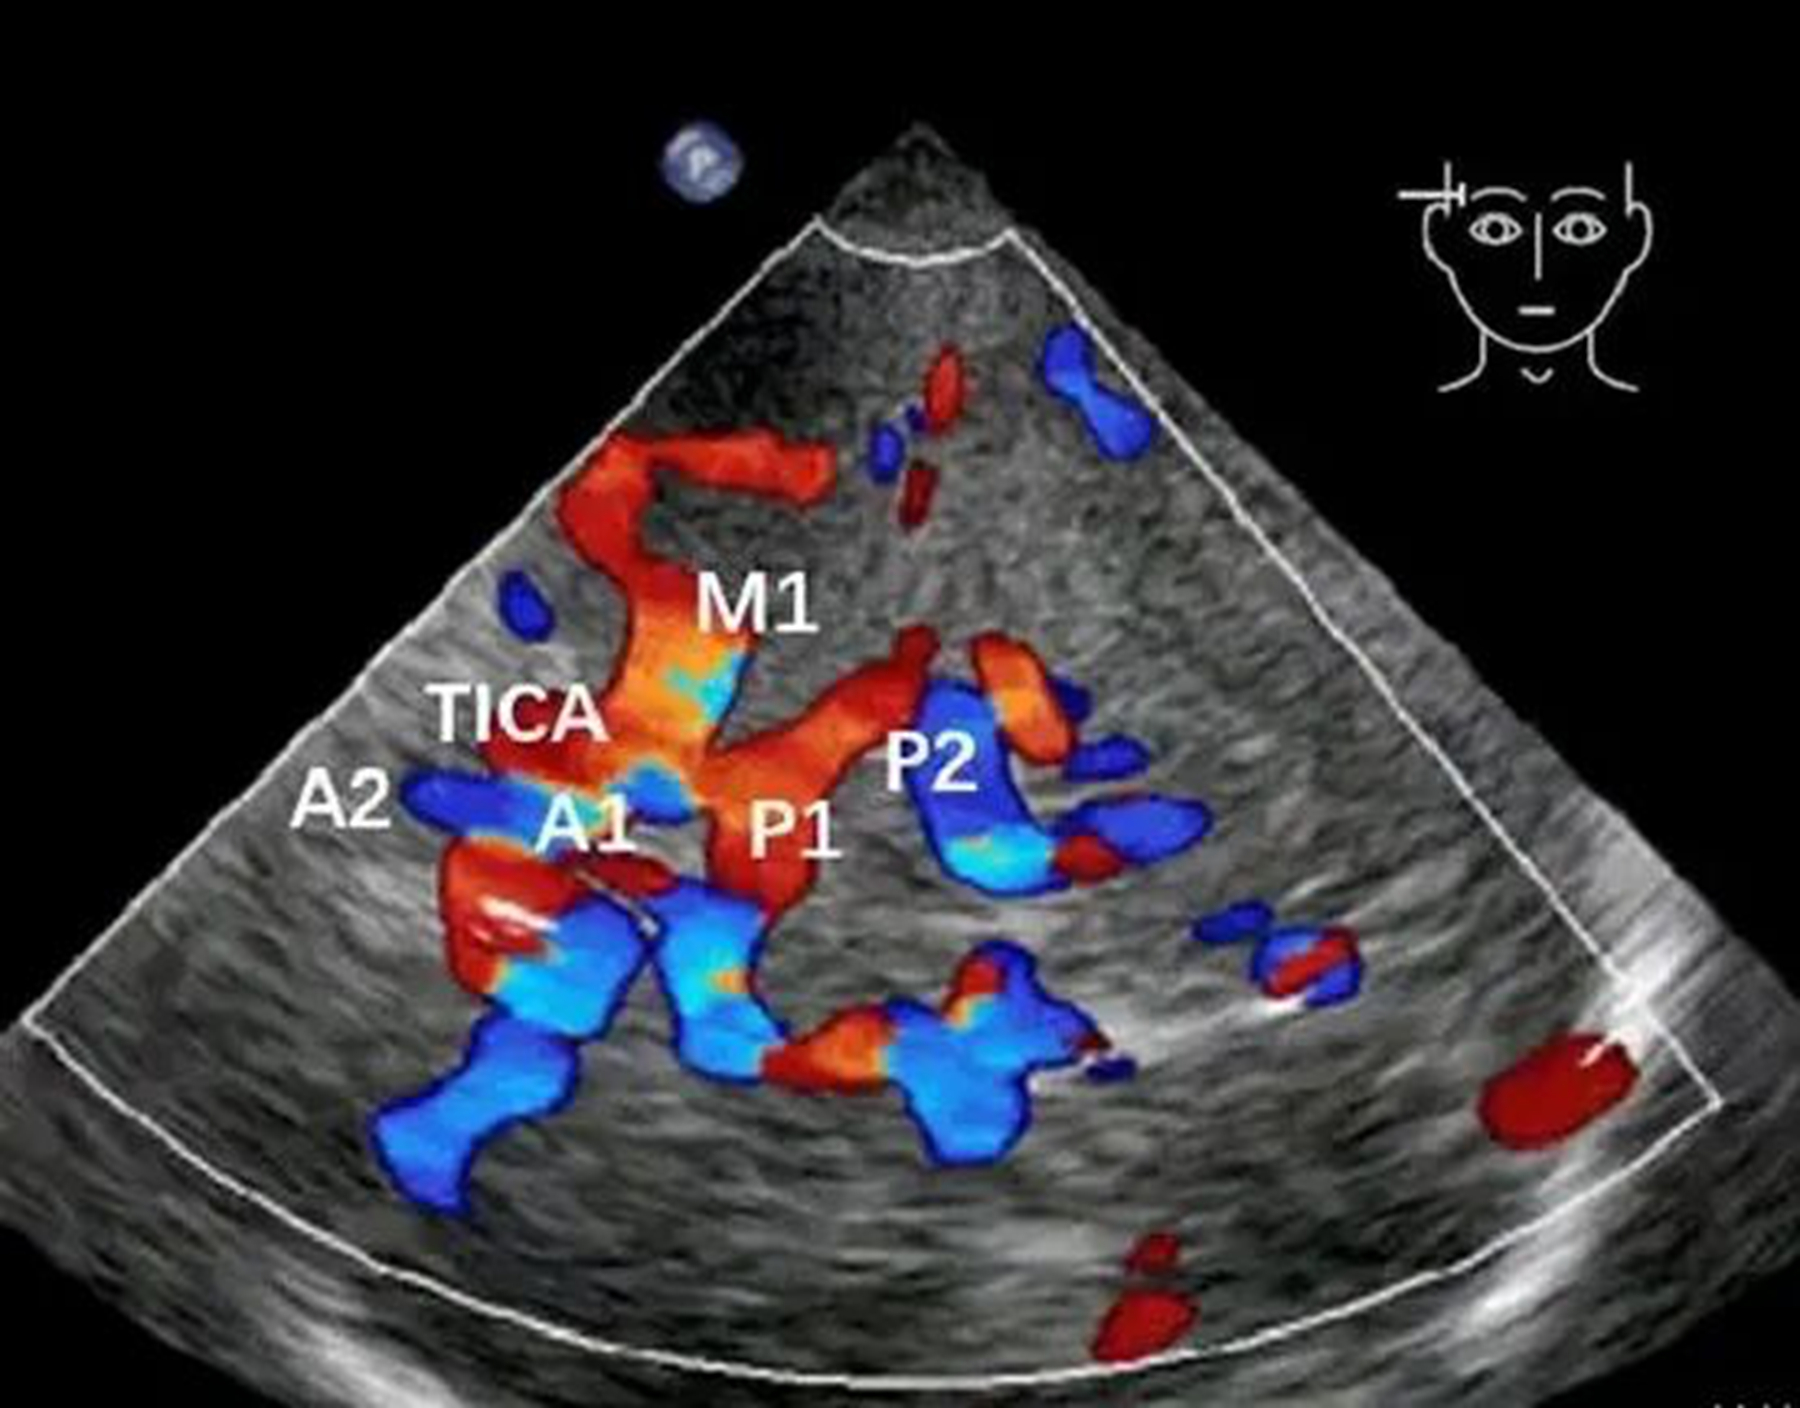

简单来说,TCCD 相当于专门为颅内血管打造的彩色 B 超。依托颅骨天然薄弱的透声窗,超声探头可穿透颅骨屏障,在显示屏上实时、动态呈现颅内各大动脉的清晰血流影像。

医生能够直观观察血管走形是否迂曲、血流速度有无异常增快、是否存在异常涡流等问题,让脑血管检查从 “只靠听” 变成 “看得见、看得清”。